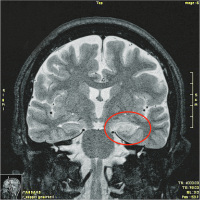

Steckbrief seltener Krankheiten: Limbische Enzephalitis mit Antikörpern gegen den Komplex spannungsabhängiger Kaliumkanäle („voltage-gated potassium channel complex“ [VGKC-Komplex])

Journal für Neurologie, Neurochirurgie und Psychiatrie 2012; 13 (3): 148-150 Volltext (PDF) Abbildungen